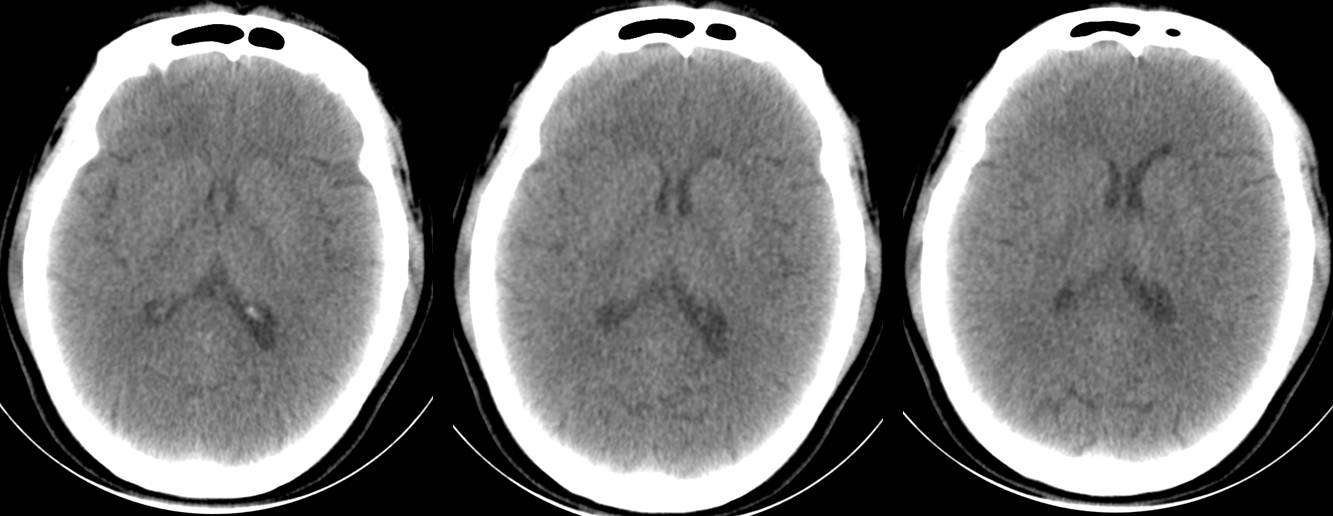

救护车载移动CT陈旧性脑梗塞扫描

救护车载移动CT扫描脑出血后软化灶形成